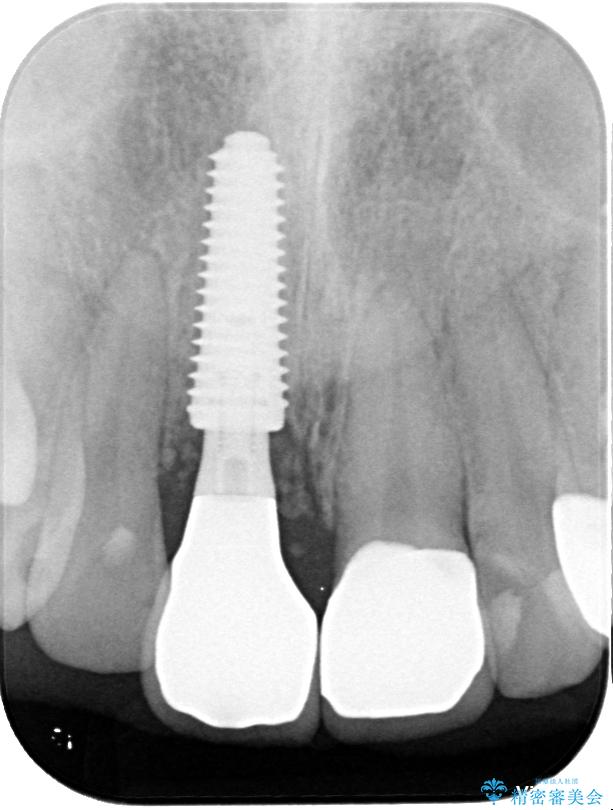

▶右上中切歯

抜歯後、即時インプラント埋入

審美性を考慮し、仮歯を即日装着

治療期間を最小限に抑えつつ、自然な前歯のラインと歯ぐきの形を維持

治療途中

• 「抜歯してブリッジ」と言われた20代女性が選んだ治療とは|たった4か月で自然な笑顔に抜歯即時インプラント+審美補綴の症例 治療途中画像